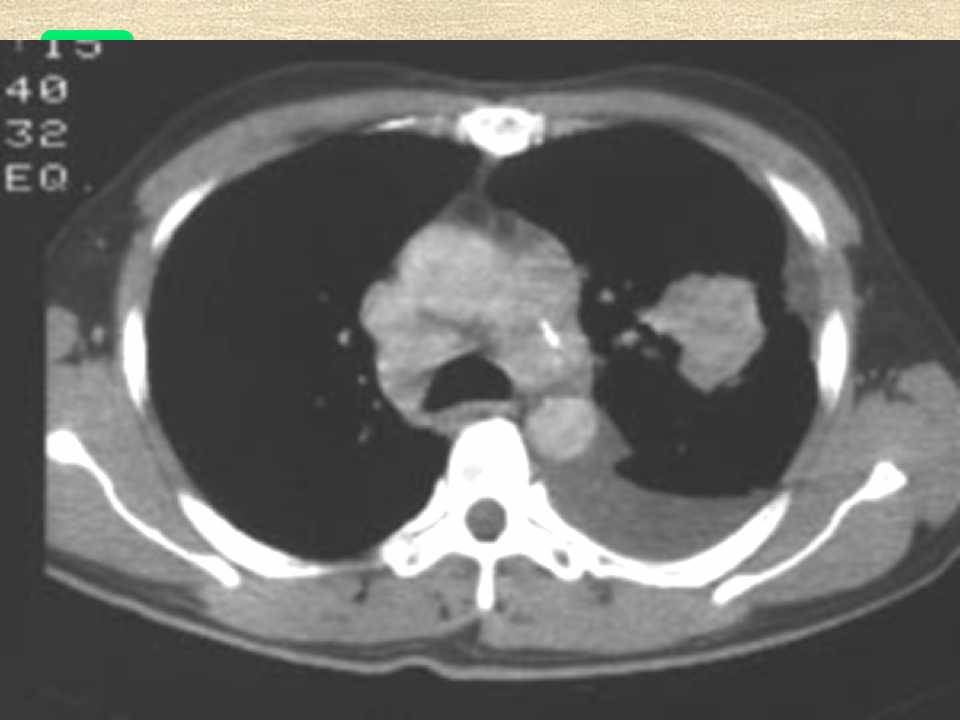

肺癌影像学表现